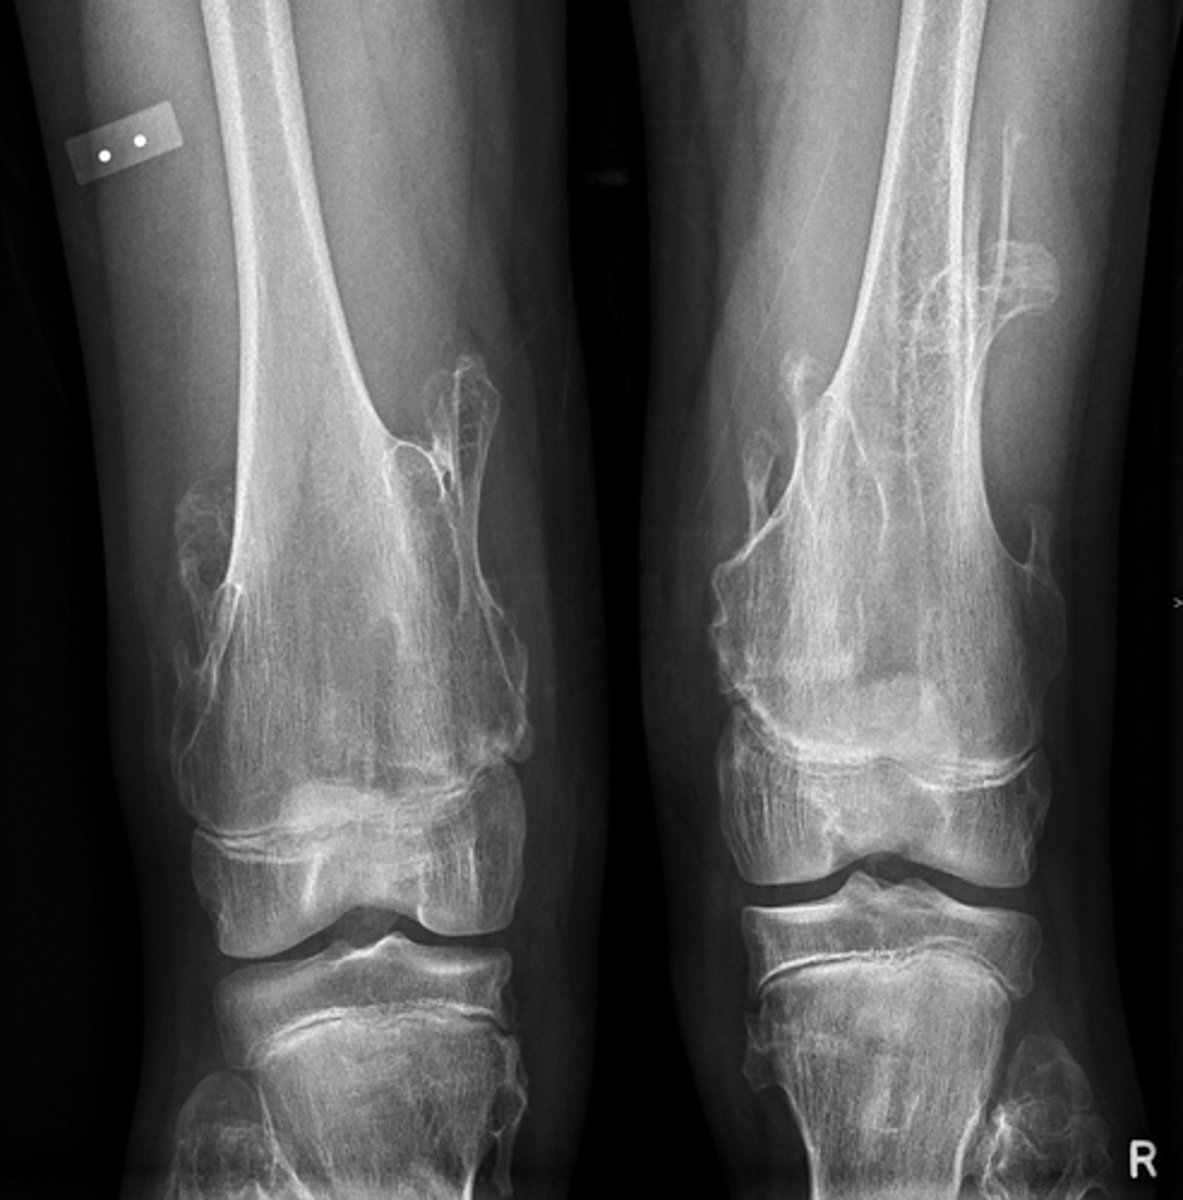

- Distal femur involved

- Elongated stalk

- Cortex and medulla are continuous

- Pointing away from joint

- Narrow base

Describe the bone lesion

<p>Describe the bone lesion</p>

Pedunculated solitary osteochondroma

Most likely diagnosis?

<p>Most likely diagnosis?</p>

- Fracture

- Malignant transformation (chondrosarcoma)

- Bursitis

- Neurologic injury

Concerns/complications?

<p>Concerns/complications?</p>

- Distal femur

- Metaphysis

- Anterolateral

- Broad base

- Cortex and medulla continuous

Sessile solitary osteochondroma

Hereditary multiple exostoses

Malignant transformation (5-25%)